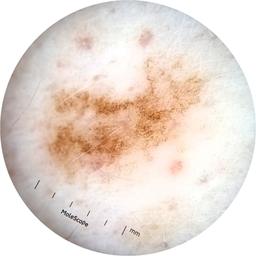

ISIC_3754278

MEL-SELF Trial, https://www.sydney.edu.au/medicine-health/our-research/research-centres/melself-project.html

Clinical

Field Value

acquisition_day 135

age_approx 65

anatom_site_1 Upper extremity

anatom_site_general upper extremity

diagnosis_1 Benign

diagnosis_confirm_type single image expert consensus

image_type dermoscopic